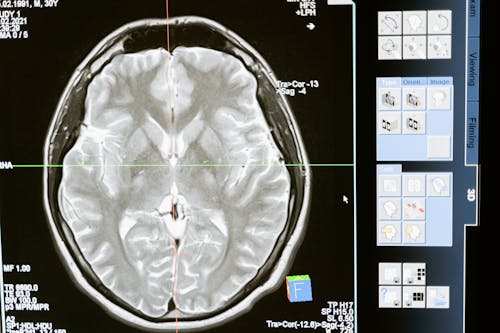

중독의 본질: 뇌의 변화와 보상 체계

먼저, 마약 중독을 이해하기 위해서는 뇌의 보상 체계에 대한 이해가 필요합니다. 마약은 뇌 속의 도파민 분비를 극도로 증가시키는데, 도파민은 우리가 기쁨이나 만족감을 느낄 때 분비되는 신경전달물질입니다. 일반적으로 도파민은 맛있는 음식을 먹거나, 운동을 하거나, 사랑하는 사람과 시간을 보낼 때 자연스럽게 분비돼요. 그러나 마약은 이 도파민 분비를 비정상적으로 높이는 방식으로 작용합니다.

이로 인해 뇌는 마약을 복용할 때만 큰 쾌락을 느끼게 되고, 그 결과로 마약 없이는 평범한 일상에서 즐거움을 느낄 수 없게 되는 상황에 빠지게 돼요. 이런 상태에서는 자연스럽게 뇌가 마약을 계속 갈망하게 되고, 점점 더 강한 용량의 마약을 필요로 하게 되는 내성이 생깁니다. 이렇게 뇌의 구조와 기능이 변화하면서 마약 없이는 정상적인 생활이 어려워지는 지경에 이르게 되는 것입니다.